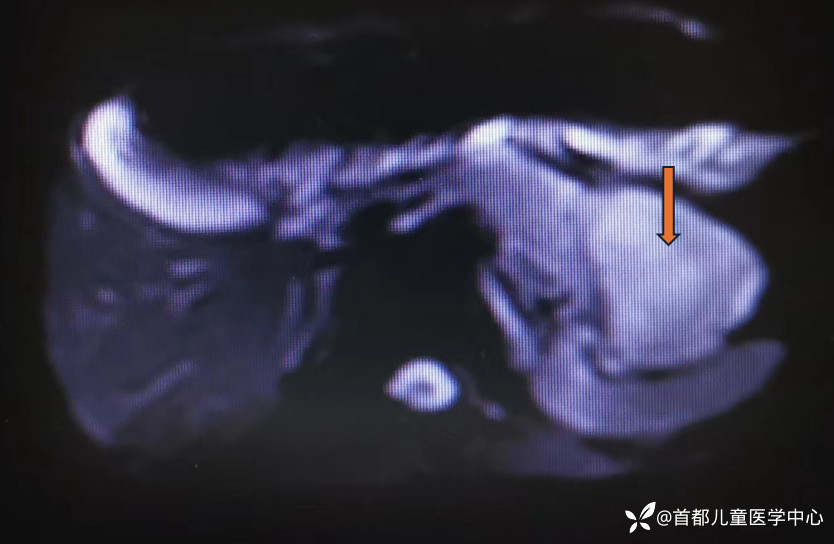

腹部CT:胰腺尾部、脾脏前方可见占位性病变,大小约4.4*5.6*6.7cm。

腹部核磁:胰腺尾部可见类圆形肿物影,呈T1W1低信号,T2WI稍高信号

腹部超声:左上腹近脾门处胰腺尾部可见一低回声包块,大小约6.7*4.1*4.8cm,内部回声强弱不等,未见钙化。